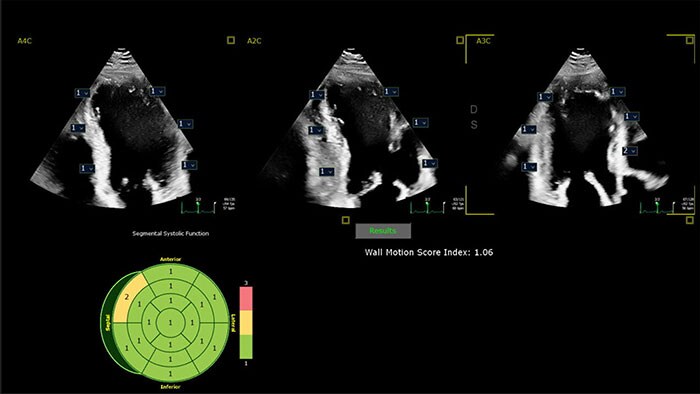

Intuitive, reproducible, AI-enabled echocardiography

Powered by AI-based capabilities, our industry-leading CV ultrasound platform delivers advanced tools for structural heart disease, including 3D automated tricuspid valve and color flow quantification tools. Efficient automation and quantification tools enable you to diagnose heart failure and coronary artery disease quickly and confidently. Tiny transducers, high frame rates and sharp imaging support confidence in pediatric echo exams. Unified on- and off-cart workflow supports lab setup and consistent UI and workflow across systems.

Philips AI-based ultrasound solutions integrate into everyday clinical workflows and are designed to make it easier and faster for clinicians to acquire, select, measure and report accurate results.